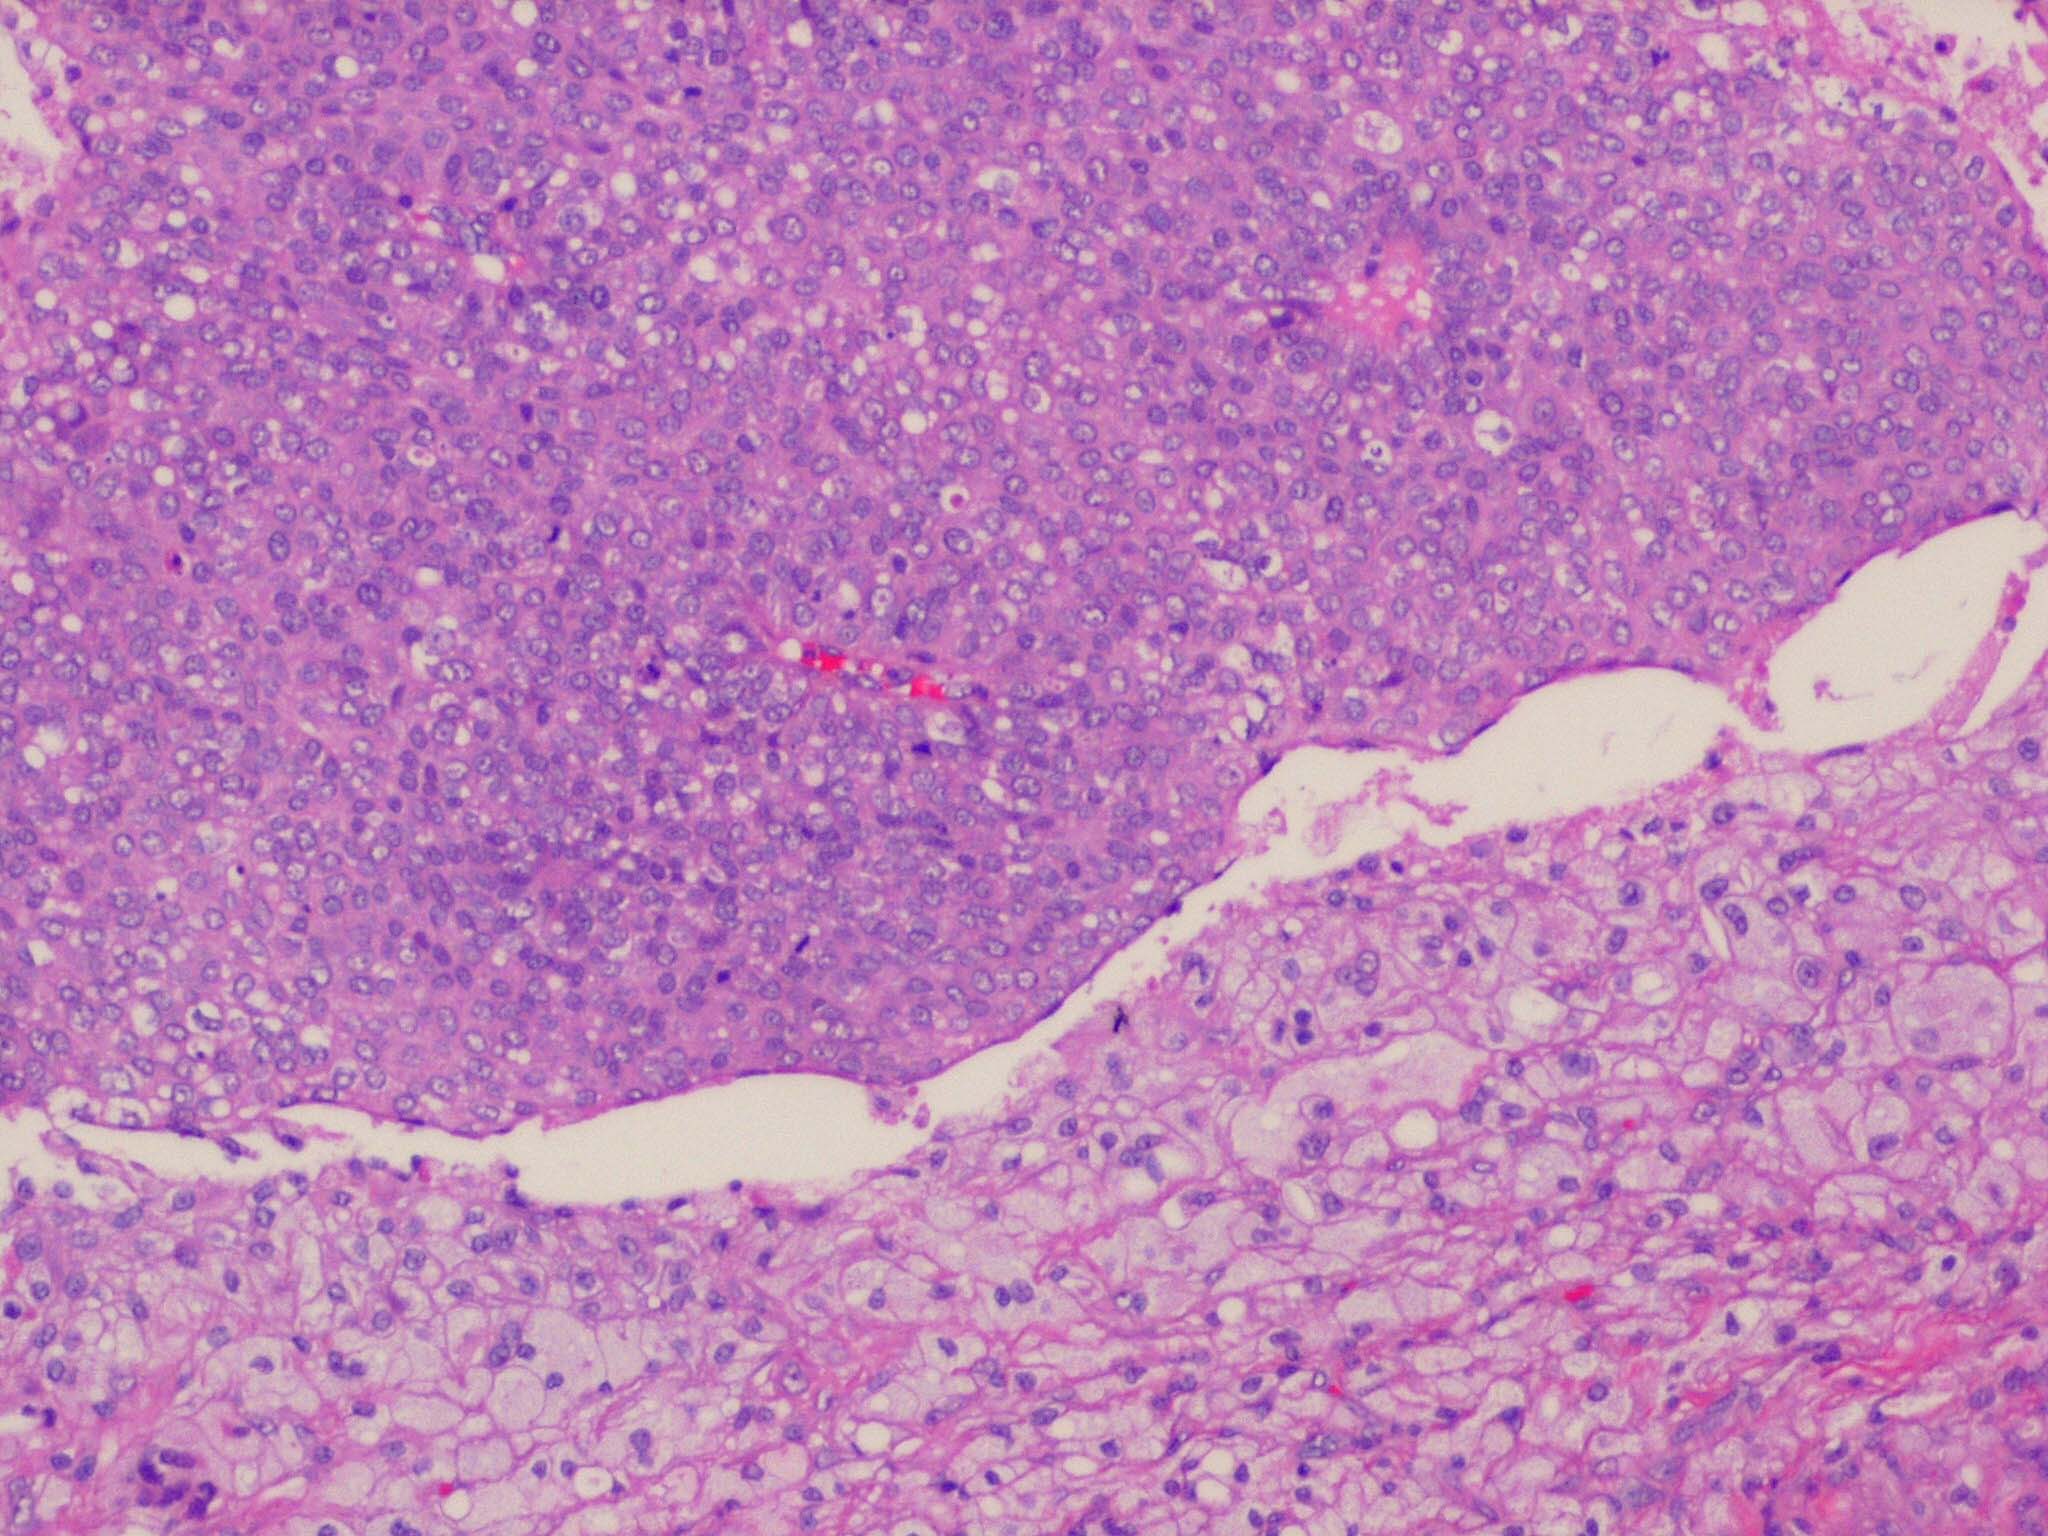

Sebaceous carcinoma = الكارسينوما الدهنية